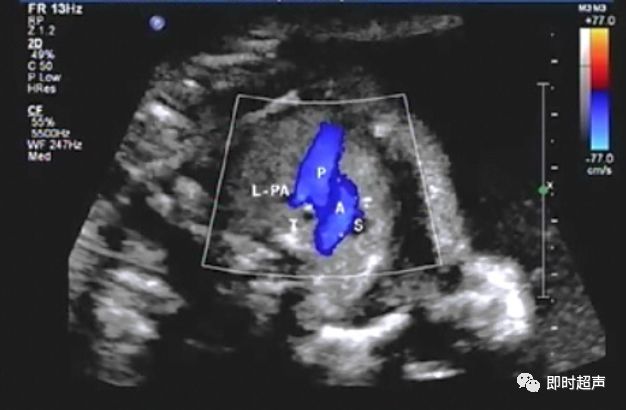

肺动脉血流反向

右心发育不良综合症(三尖瓣或肺动脉瓣闭锁或重度狭窄)

主动脉弓或肺动脉血流方向相反是导管依赖型心脏畸形的典型表现

动脉导管依赖型心脏畸形,是指出生时新生儿的存活依赖于动脉导管的开放,如果动脉导管闭锁了,那么体循环和肺循环之间的沟通也就终止了,新生儿就会迅速死亡的一类心脏畸形。

诊断动脉导管依赖型心脏畸形的意义?

一旦存在动脉导管依赖型心脏畸形,就是十分严重的心脏畸形,一般而言都应该终止妊娠。但对仍要继续妊娠的孕妇而言,意义就更加重大,因为对新生儿而言,保持动脉导管的开放等待紧急手术是它们唯一的生命线。